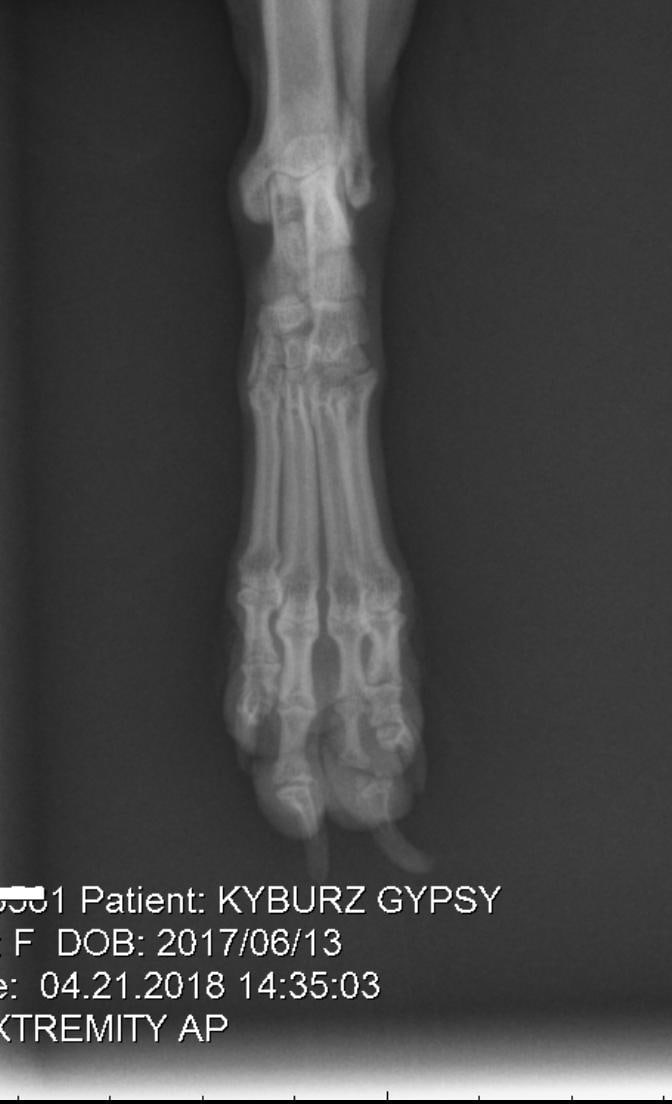

Took my 10 month old yorkie puppy to the vet today as her rear paw pad looked strange (see photo). They did X-rays and determined it's a congenital defect with the bone. They want to amputate her toe. Looking for Second opinion. I have attached photos of the x-rays

If the toe is causing Gypsy pain or if it is causing medical problems, then amputation may be the proper way to go. If it is not causing her any problems or pain, then I see no reason why the toe needs to be amputated. That said, I have not seen your puppy in person nor have I been able to examine the paw for problems. So I can only go by what I see on the x-ray and photo.